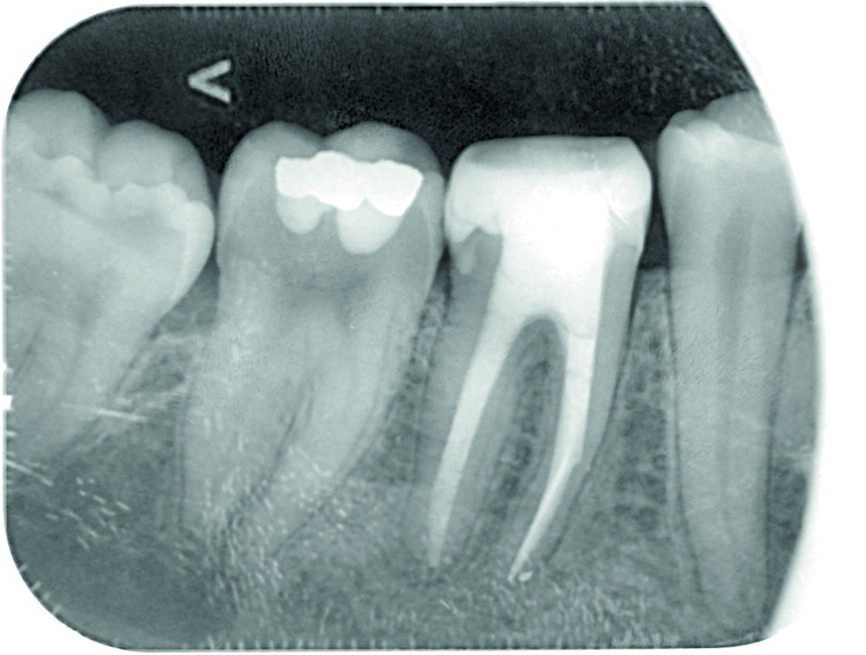

A 34-year-old female patient was referred for endodontic treatment of tooth #46 because of a separated endodontic instrument in the mesial root, which was observed on the initial radiograph (Fig. 1). The patient’s chief complaint was mild pain in the mandibular right posterior region during chewing. She gave a history of a root canal therapy on the same tooth four years earlier. There was no other relevant medical history.

Fig. 1: Initial radiographic status of tooth #46